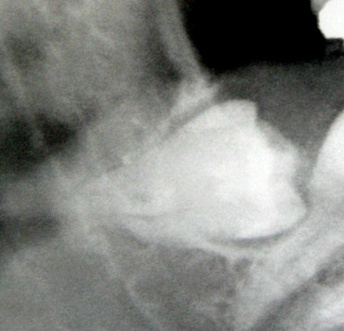

Ο βλεννογόνος του χείλους γίνεται επίσης αντικείμενο μηχανικού τραυματισμού. Μια ανατομική δομή που συνήθως τραυματίζεται στην περιοχή του χείλους είναι οι μικροί σιαλογόνοι αδένες. Το τελικό αποτέλεσμα είναι η λεγόμενη βλεννοκήλη (Εικόνα 6).

Εικόνα 6. α. Βλεννοκήλη κάτω χείλους (βέλος), β. Αμέσως μετά την χειρουργική της αφαίρεση.